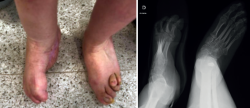

Tras la retirada del fijador y la inmovilización, se autorizó la carga. La paciente presenta un pie plantígrado e indoloro sin complicaciones asociadas (Figura 4).

Además, se observa una normalización del ángulo de Meary y el de Costa-Bartani (Figura 5).

Figura 5. Radiografías en carga que muestran la normalización de los ángulos de Meary y Costa-Bartani.

El valor normal del ángulo de Meary sería menor de 10° y nos sirve para evaluar la alineación del arco longitudinal medial del pie y cuantificar deformidades sagitales(11).

El valor normal del Costa-Bartani es entre 120 y 130°, y evalúa la altura y la estabilidad del arco medial, y el equilibrio estructural del pie(12).

Al año de la cirugía, la paciente se encuentra deambulando de manera autónoma y sin ayudas, con un buen resultado global a nivel clínico y radiológico.

Figura 4. Pie corregido.